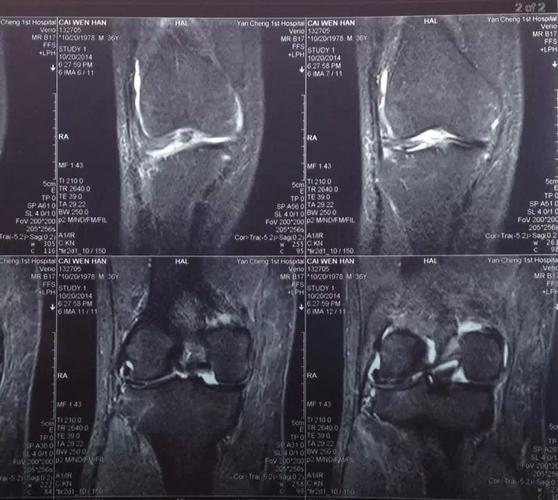

半月板损伤核磁共振图

半月板损伤核磁共振图,半月板损伤静养姿势

踢球受伤求助!请骨科专家来帮我看看我的左边膝盖核磁共振的片子!

膝关节的鉴别诊断 半月板损伤 mri规范化扫描 mri磁共振片子 南昌大学

半月板损伤磁共振图解

半月板核磁共振图解析

半月板磁共振图解

半月板3度撕裂共振图

半月板损伤片子

膝关节半月板损伤图